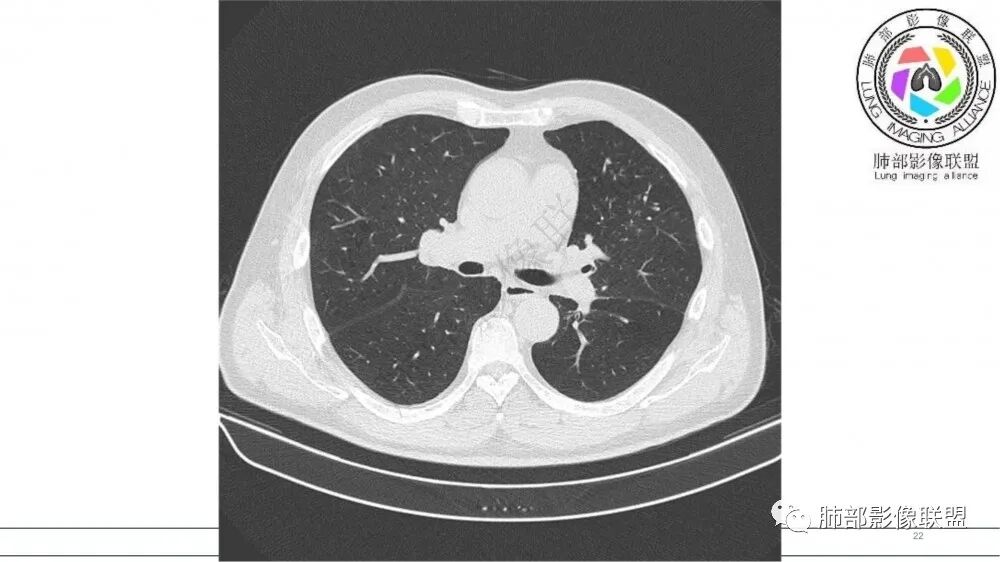

指套征明确吧

有强化吧,淋巴结大

指套征,扩张支气管内软组织强化,远侧肺野阻塞性炎,纵隔、左肺门肿大淋巴结;老年男性,吸烟,考虑鳞癌,鉴别小

老年吸烟男性,尖前段支气管内塑形生长,增粗蠕虫样,没有肺不张(排除鳞癌?),远端少许阻塞肺炎,增强低强化,锁定小

老年男性,吸烟,指套征,蠕虫征,阻塞性炎症不严重。可见血管穿行,密度均匀,轻度强化,首先考虑小细胞肺癌。鉴别鳞

指套征:是影像征象,胸部平片表现为手指状密度增高影,以肺门为中心呈放射状分布,CT显示扩张支气管内低密度黏液栓形成或实性病变,呈管状、树枝状或卵圆形密度增高影;支气管扩张伴近端梗阻时,扩张支气管内部黏液分泌物不能排出而形成。可以伴随远端空气潴留征、阻塞性炎症。